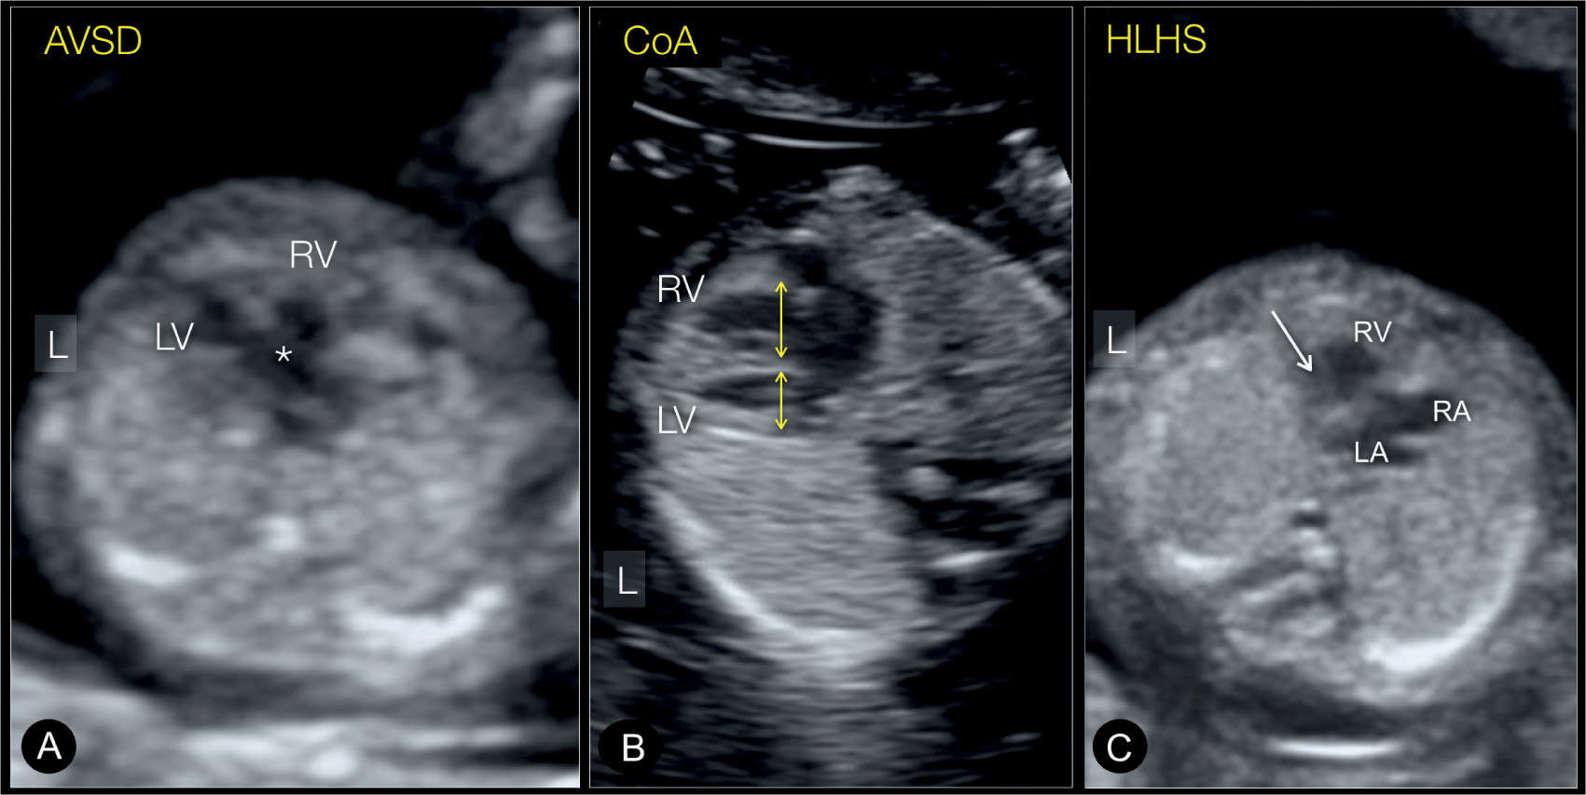

Fetal Cardiac Examination in Early Gestation Obgyn Key What Can Cause A Fetus To Be Smaller Than Normal If your baby is very small when it's born, your doctor can give it oxygen through a nose tube, fluids through a tube in a vein and, sometimes,. Babies are diagnosed with intrauterine growth restriction (iugr) if they appear to be smaller than expected. Fetal growth restriction (fgr) is a condition in which an unborn baby (fetus) is smaller than. What Can Cause A Fetus To Be Smaller Than Normal.